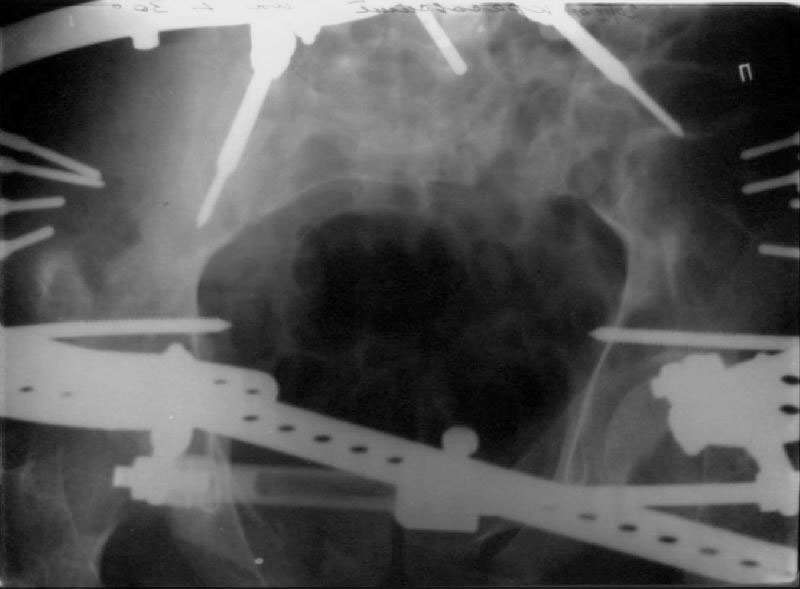

An example of our current approach to similar injuries - A 26 y.o. male admitted to us Aug 23, 2001 6 weeks after injury (compression by a wheel of a truck).

An external fixator was applied and gradual reduction was started - lateral traction to mobilize sacral fracture and then the hemipelvis was moved downward. Then lateral compression was performed. Yesterday iliosacral screws was inserted.

The last couple of images are skewed, they were made in OR and patient was not properly positioned.